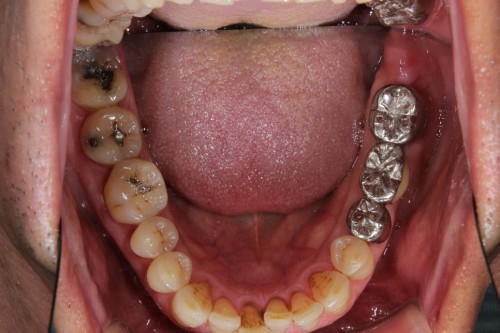

両奥に白い詰め物で治療してありますが、詰め物の周りが茶色に着色しています。また、本来の歯の形とはずいぶん違うみたいです。奥歯で噛んだ感じに違和感があるとの事でしたので、治療致しました。本来歯が持っている形をお口の中で作って行きます。

治療後です。どこを治療したのかわからないくらい『自然の歯』の様にできました。噛む時の違和感もなくなり、硬い物でも噛める様になりました。

左右奥歯のダイレクトボンディング

費用5万円×2本

リスクとして欠ける可能性がある(修復可能)。